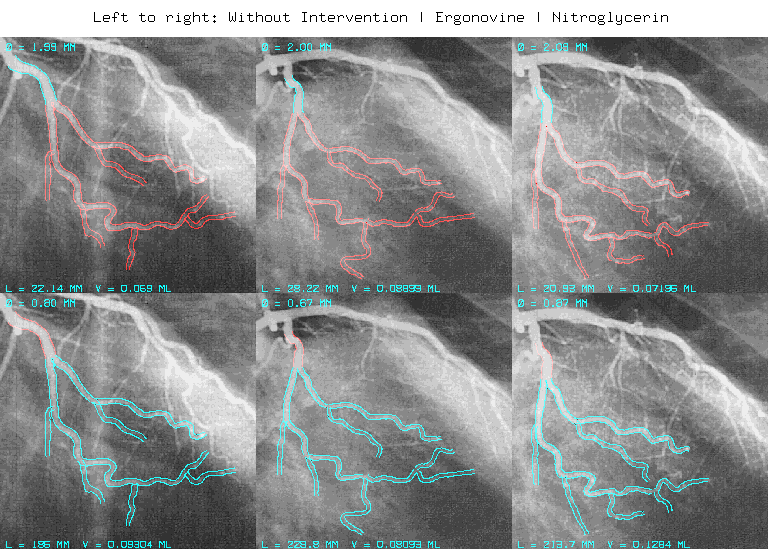

Influence of Vasoactive Medication